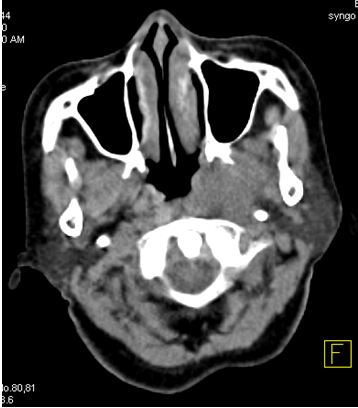

Mô phỏng tốt nhất trên PET/CT với hệ thống laser định vị 3 chiều. Vì PET/CT ghi hình dựa trên sự tập trung cao thuốc phóng xạ FDG vào các tế bào ung thư, cho hình ảnh chuyển hóa của khối u, sớm, chính xác hơn hình ảnh giải phẫu của CT đơn thuần (hình 1), xác định được mức độ xâm lấn của u cũng như phát hiện những di căn hạch kể cả với kích thước nhỏ ở mức độ phân tử, mức độ tế bào từ đó cho phép xác định thể tích xạ trị cũng như việc lập kế hoạch xạ trị được triệt để nhất (hình 2). Khi chụp mô phỏng: bệnh nhân trong tư thế nằm ngửa, cổ ưỡn sao cho đường thẳng giữa cằm - xương chũm vuông góc với mặt bàn; đầu bệnh nhân được giữ cố định bằng mặt nạ, tổng hợp từ loại chất dẻo đặc biệt.

Hình ảnh CT mô phỏng khó xác định được vị trí khối u

Hình ảnh PET/CT mô phỏng thấy rõ khối u vòm

Hình 1: Hình CT và PET/CT mô phỏng ung thư vòm.